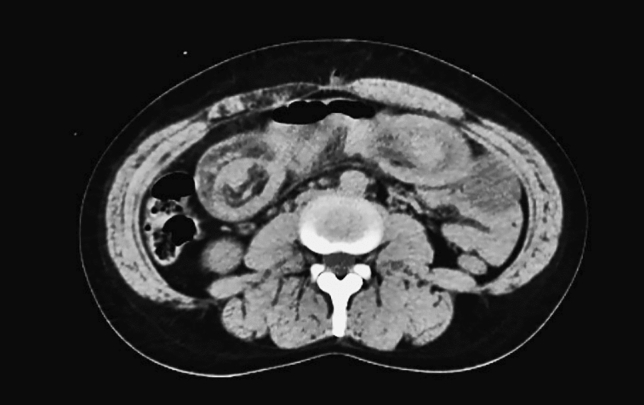

Methods and Procedures: Twenty-four patients underwent abdominal wall reconstruction (AWR) between January 2017 and June 2022 by a single surgeon at our institution. Lifestyle information (smoking, diabetes, and obesity status) and procedure-related metrics (pre-operative botox use, hernia characteristics, and mesh type) were obtained. The ellipsoid formula (V = 4/3ABC) was used to calculate volume of the hernia sac (VIH) and abdominal cavity (VAC) (Fig. 1). Measurements at initial visit and time of surgery were compared and analyzed using a two-tailed T Test (p < 0.05 signified significance).

Fig. 1 Hernia sac measurements for calculating VIH (Left to right: axial, sagittal, coronal)